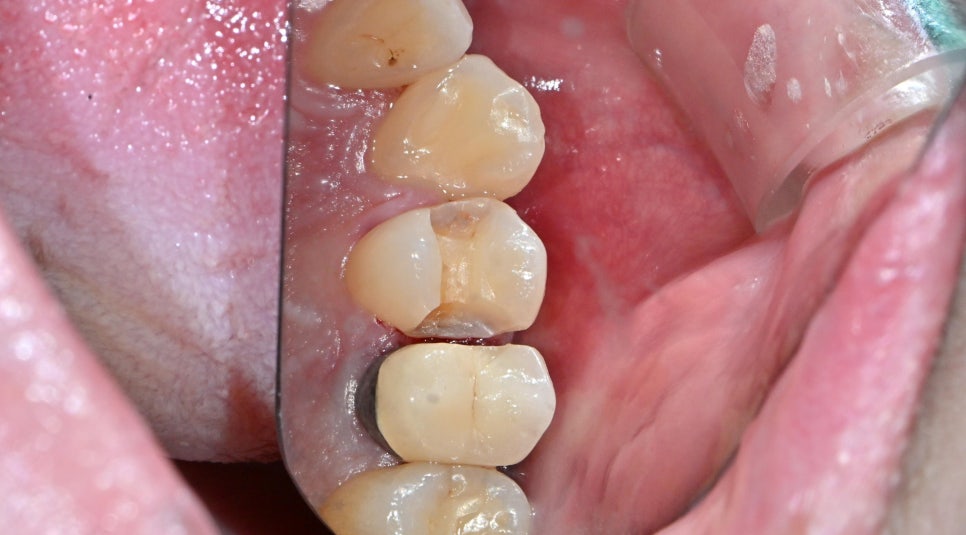

마곡동치과_인접면 충치 삭제

바로 위 사진처럼 충치로 손상된 부위를 삭제해 줍니다.

여기까지는 기존 인레이 치료와 크게 다르지 않습니다.

하지만 지금부터가 디아치과만의 진짜 차별점이 시작됩니다!